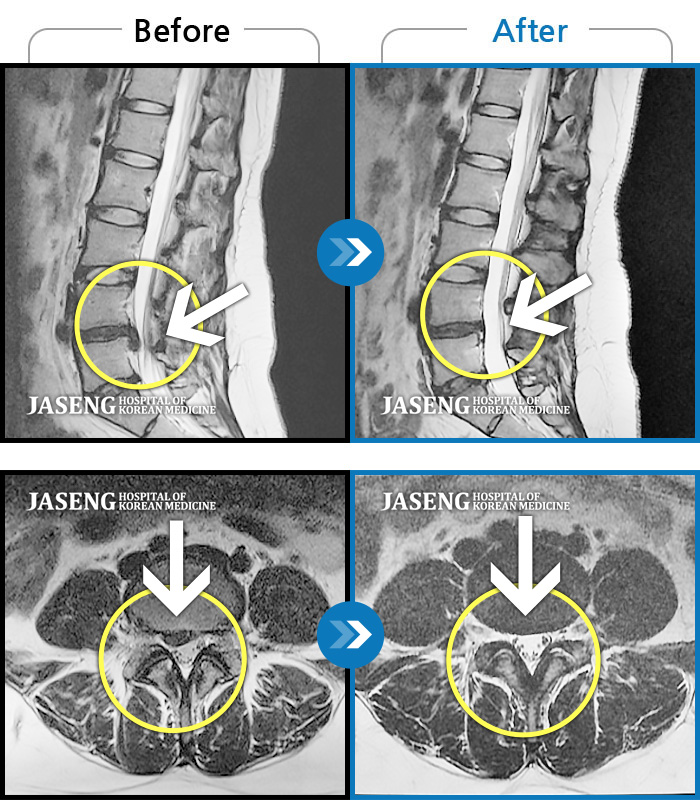

MRI 치료사례

허리 및 우측 하지 통증